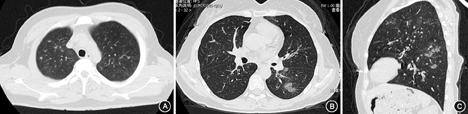

30例患者中27例(90.0%)行胸部CT检查,其中CT平扫18例,高分辨率CT(HRCT)扫描9例。主要表现为磨玻璃影、肺结节影、支气管壁增厚、支气管扩张、胸膜增厚、肺实变、肺不张。肺外影像学表现中最常见纵隔淋巴结增大,有3例出现浅表淋巴结增大,主要分布在颈部、腋窝、腹股沟区(图1,表3)。

注:A:双肺小结节影和磨玻璃影(CT平扫);B:左肺下叶磨玻璃样改变(高分辨率CT);C:左肺磨玻璃样改变和支气管壁增厚、支气管扩张(高分辨率CT)

EGPA病程分3期:前驱期、嗜酸性粒细胞浸润期、血管炎期,各期之间无明显界限[11]。有专家共识提出EGPA可分为局限型及全身型,前者指仅累及肺部和呼吸道(包括耳鼻喉)[12]。大多数局限型患者易误诊为难治性嗜酸性粒细胞性哮喘,应完善胸部影像学。本研究中,患者肺部一过性磨玻璃影最常见,其他常见表现有肺结节影、支气管壁增厚、支气管扩张。肺外表现中以纵隔淋巴结增大多见。有研究总结EGPA肺内病变主要表现为:磨玻璃密度影、实变影、结节影、小叶间隔增厚、支气管壁增厚;肺外病变可见纵隔或肺门淋巴结肿大、单或双侧胸腔积液、心影增大、心包增厚、心包积液等[13]。HRCT可发现X线片不能显示的一些早期病变,且显示EGPA肺内病变的细节优于常规CT,可降低漏诊率。本组27例行胸部CT检查,其中1/3行HRCT检查。